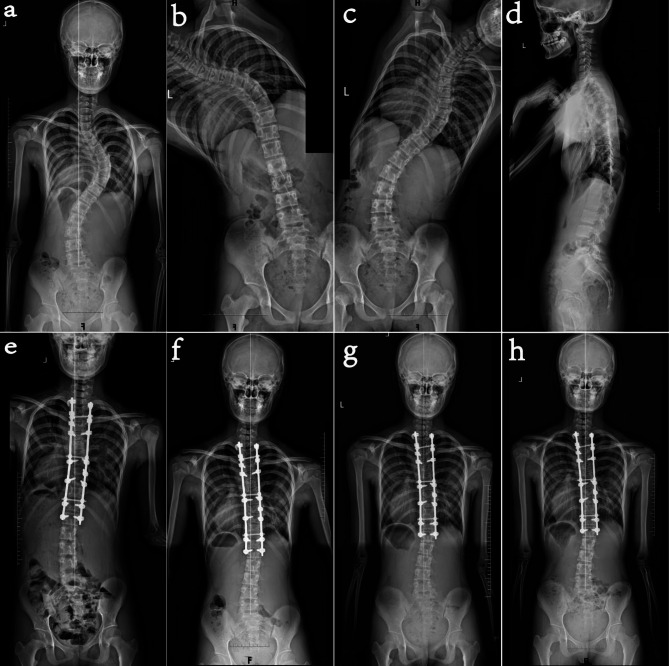

探讨Lenke 1型和2型青少年特发性脊柱侧凸(AIS)患者后路选择性胸椎融合术后远端附加现象进展的相关危险因素。对2015年12月至2021年12月期间接受后路选择性胸椎融合术的152例患者进行回顾性分析。其中48例患者术后出现远端附着现象。根据这种现象在随访中是否进展分为进展组和非进展组。单因素分析比较了两组之间的临床和影像学资料,而多因素logistic回归确定了独立的危险因素。48例术后远端接物患者中,37例(77.1%)为非进展性,11例(22.9%)为进展性。单因素分析显示,进展组和非进展组在Risser体征分级上存在显著差异(2.27±1.10∶3.73±0.87,P

To investigate risk factors associated with the progression of the distal adding-on phenomenon after posterior selective thoracic fusion in patients with Lenke type 1 and 2 adolescent idiopathic scoliosis (AIS). A retrospective analysis was conducted on 152 patients who underwent posterior selective thoracic fusion from December 2015 to December 2021. Among them, 48 patients experienced the distal adding-on phenomenon postoperatively. Based on whether this phenomenon progressed during follow-up, they were divided into progressive and non-progressive groups. Univariate analysis compared clinical and imaging data between the two groups, while multivariate logistic regression identified independent risk factors. Of the 48 patients with postoperative distal adding-on, 37 (77.1%) were non-progressive and 11 (22.9%) were progressive. Univariate analysis showed significant differences between the progressive and non-progressive groups in Risser sign grade (2.27 ± 1.10 vs. 3.73 ± 0.87, P < 0.001), number of segments between lowest instrumented vertebra (LIV) and the last substantially touched vertebra (LSTV) (-1.27 ± 0.79 vs. 0.51 ± 1.17, P < 0.001), preoperative clavicle angle (-2.55 ± 2.84 vs. -0.11 ± 2.82, P = 0.015), and preoperative trunk shift (21.05 ± 15.27 vs. 10.46 ± 13.32, P = 0.030). Multivariate analysis confirmed that lower Risser sign grade (OR = 0.16, 95% CI 0.03-0.82, P = 0.028) and fewer segments between LIV and LSTV (OR = 0.07, 95% CI 0.01-0.58, P = 0.013) were independent risk factors for the progression of the distal adding-on phenomenon. Lower skeletal maturity (Risser sign grade) and LIV located cephalad to LSTV are independent risk factors for the progression of the distal adding-on phenomenon in patients with Lenke type 1 and 2 AIS. For skeletally immature patients (Risser ≤ 3), LSTV should be preferentially chosen as LIV during surgery.